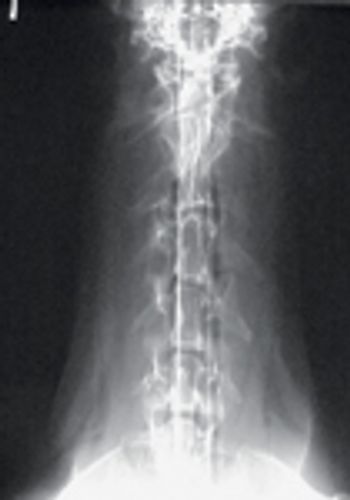

Angular limb deformities are common orthopedic conditions in dogs, and a wide variety of deformities can occur. These deformities have most commonly been described in the canine antebrachium.